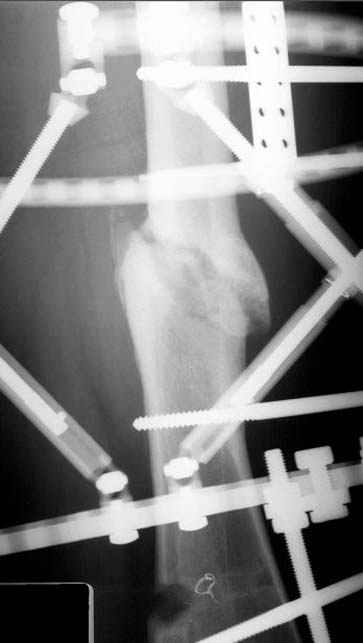

пластическая модель; и коррекция бедра аппаратом Илизарова.